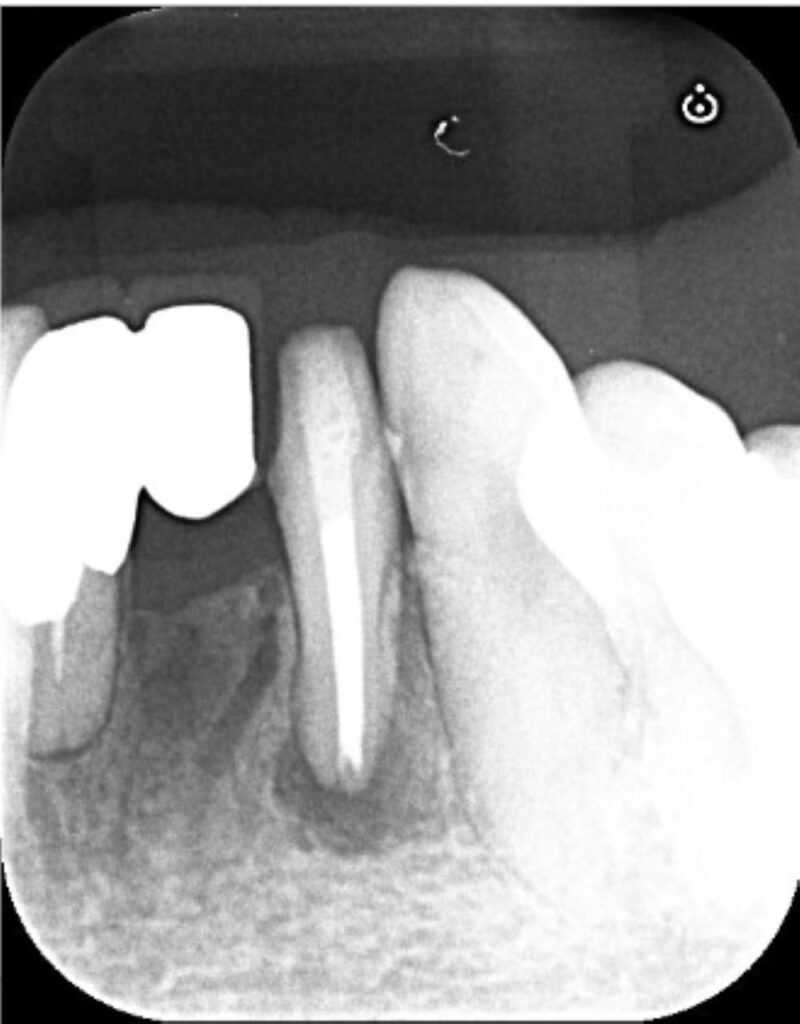

6ヶ月後の経過観察

術前にはっきり写っていた根の先の黒い影は術後6ヶ月でほぼ消失しており、骨の回復が認められます。患者様の症状も痛み・腫れともに完全に消え、良好な状態でした。根の問題は解決したため、このまま最終補綴(セラミックのブリッジ)へ移行することになりました。

6ヶ月の経過観察時には骨はほとんど回復しており、経過良好といえます。